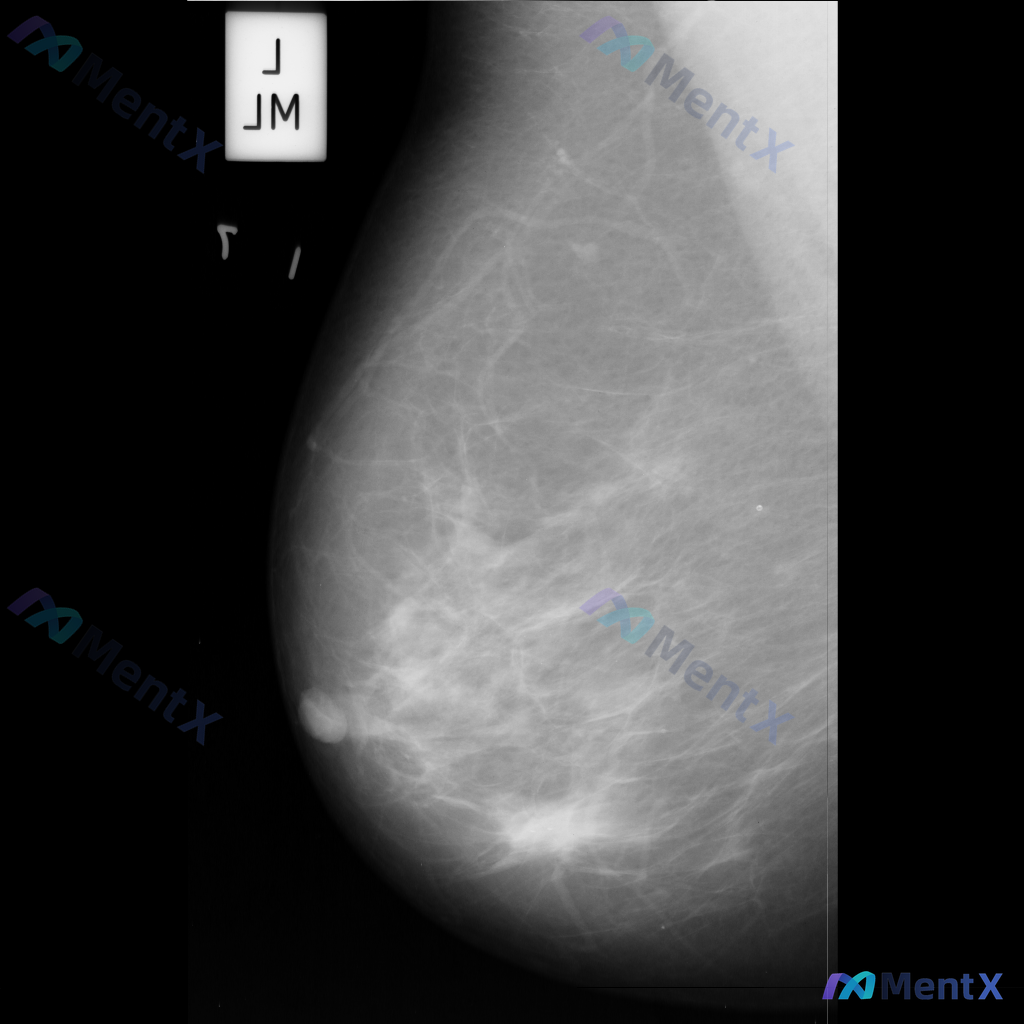

各位同道好,今天分享一则左乳钼靶病例,影像表现如下: 1. 左乳下方(近乳头区)可见一个边界清晰、形态卵圆形的等/稍高密度肿块影; 2. 左乳中央及下象限腺体局部密度增高和结构紊乱; 3. 散在分布的粗大点状钙化。 上传的钼靶影像编号为mdb083.png,供大家参考。 针对这组表现,你更倾向于哪种...

整理到一张乳腺钼靶影像的读片资料,想和大家讨论一下。 影像显示:左乳下象限可见一个不规则形、高密度的肿块,边缘模糊且部分区域有毛刺样改变;肿块区域内有散在分布的微小多形性钙化点,呈簇状分布;肿块周围还可见乳腺腺体结构紊乱和牵拉。 目前没有提供患者的既往病史、临床症状或其他检查结果。 单看这张影像的异...